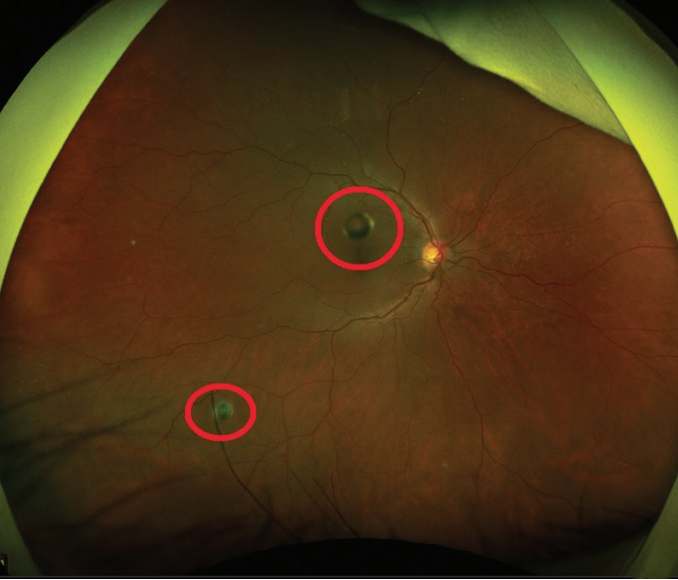

Reports of symptomatic silicone oil droplets accumulating in the vitreous cavity immediately upon injection occurred in the early days of intravitreal injection,1,2 and reports of silicone oil droplets following injection of compounded bevacizumab (Avastin, Genentech) can be found in the more recent literature (Figure).3,4 These have been attributed to silicone oil used as a lubricating agent in needles and syringes. The oil droplets should not be confused with a contamination or complication of the medication itself, but rather are secondary to the repackaging of the medication in polypropylene syringes lined with silicone oil.

Figure. Ultra-widefield color fundus photographs taken with the California (Optos) highlighting silicone oil droplets (red circles) in three patients receiving intravitreal bevacizumab (Avastin, Genentech). Commonly, these droplets are described as symptomatic vitreous opacities consisting of a dark ring surrounding a bright center. Note the varying sizes and appearances.